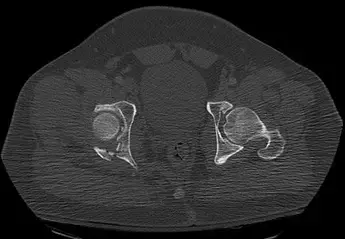

- الأشعة السينية (X-rays): هي أول فحص يتم إجراؤه عادة لاستبعاد وجود أي كسور في العظام، حيث أن أعراض التواء الكاحل يمكن أن تتشابه مع أعراض الكسر.

- التصوير بالرنين المغناطيسي (MRI): ليس ضرورياً في جميع حالات التواء الكاحل، ولكنه مفيد جداً في حالات الالتواء الشديد (الدرجة الثالثة)، أو عندما يشتبه الدكتور هطيف في وجود إصابات أخرى في الأنسجة الرخوة مثل تمزق الغضاريف، أو إصابة الأوتار، أو لتحديد مدى دقة تمزق الأربطة، أو في حال عدم استجابة الكاحل للعلاج التحفظي. يساعد التصوير بالرنين المغناطيسي الدكتور هطيف على رؤية الأربطة والأوتار والأنسجة الرخوة بوضوح لتخطيط أفضل مسار للعلاج.

- الموجات فوق الصوتية (Ultrasound): يمكن استخدامها أيضاً لتقييم الأربطة والأوتار، وتكون مفيدة في بعض الحالات.